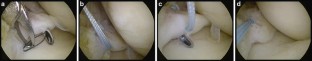

Fig. 3